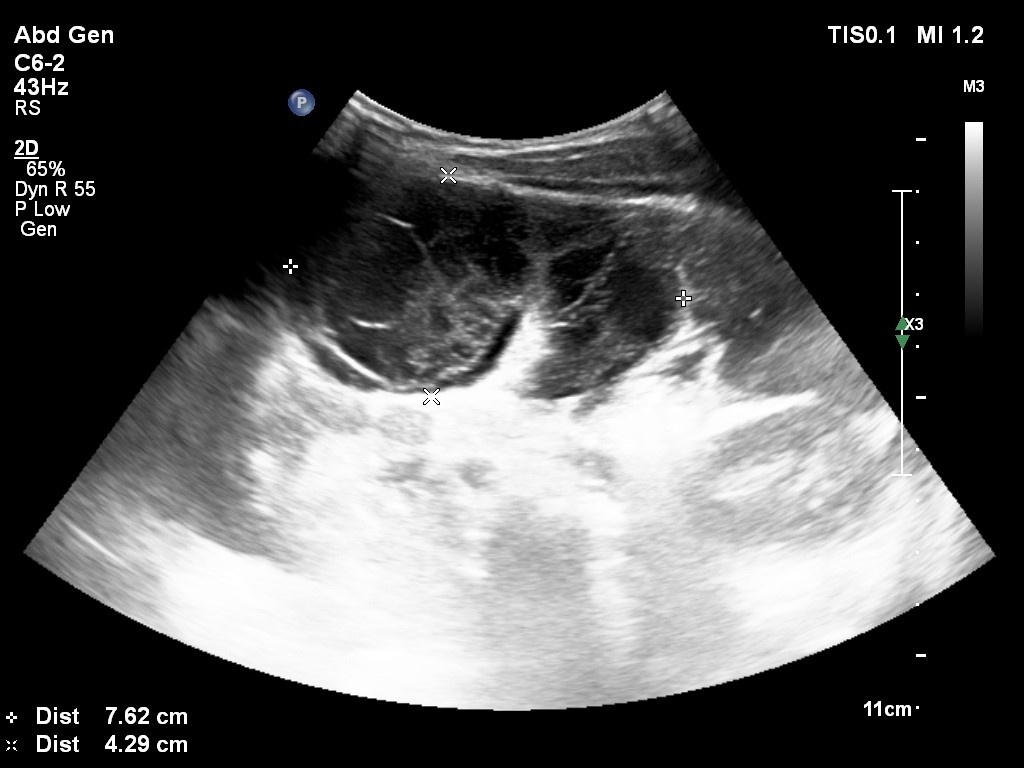

Kết quả siêu âm cho thấy tại đây có cấu trúc giảm âm dạng nang dịch, kích thước 11x8x5 cm, thành mỏng, bên trong có dịch vách hóa, đè đẩy đại tràng xuống ra đằng sau. Ngoài ra, ổ bụng bệnh nhi có ít dịch tự do đồng nhất. Hình ảnh siêu âm nghĩ nhiều đến u nang mạc treo (lymphangioma).

Hình ảnh siêu âm của bệnh nhi cho thấy dấu hiệu của u mạc treo. Ảnh: BVCC.